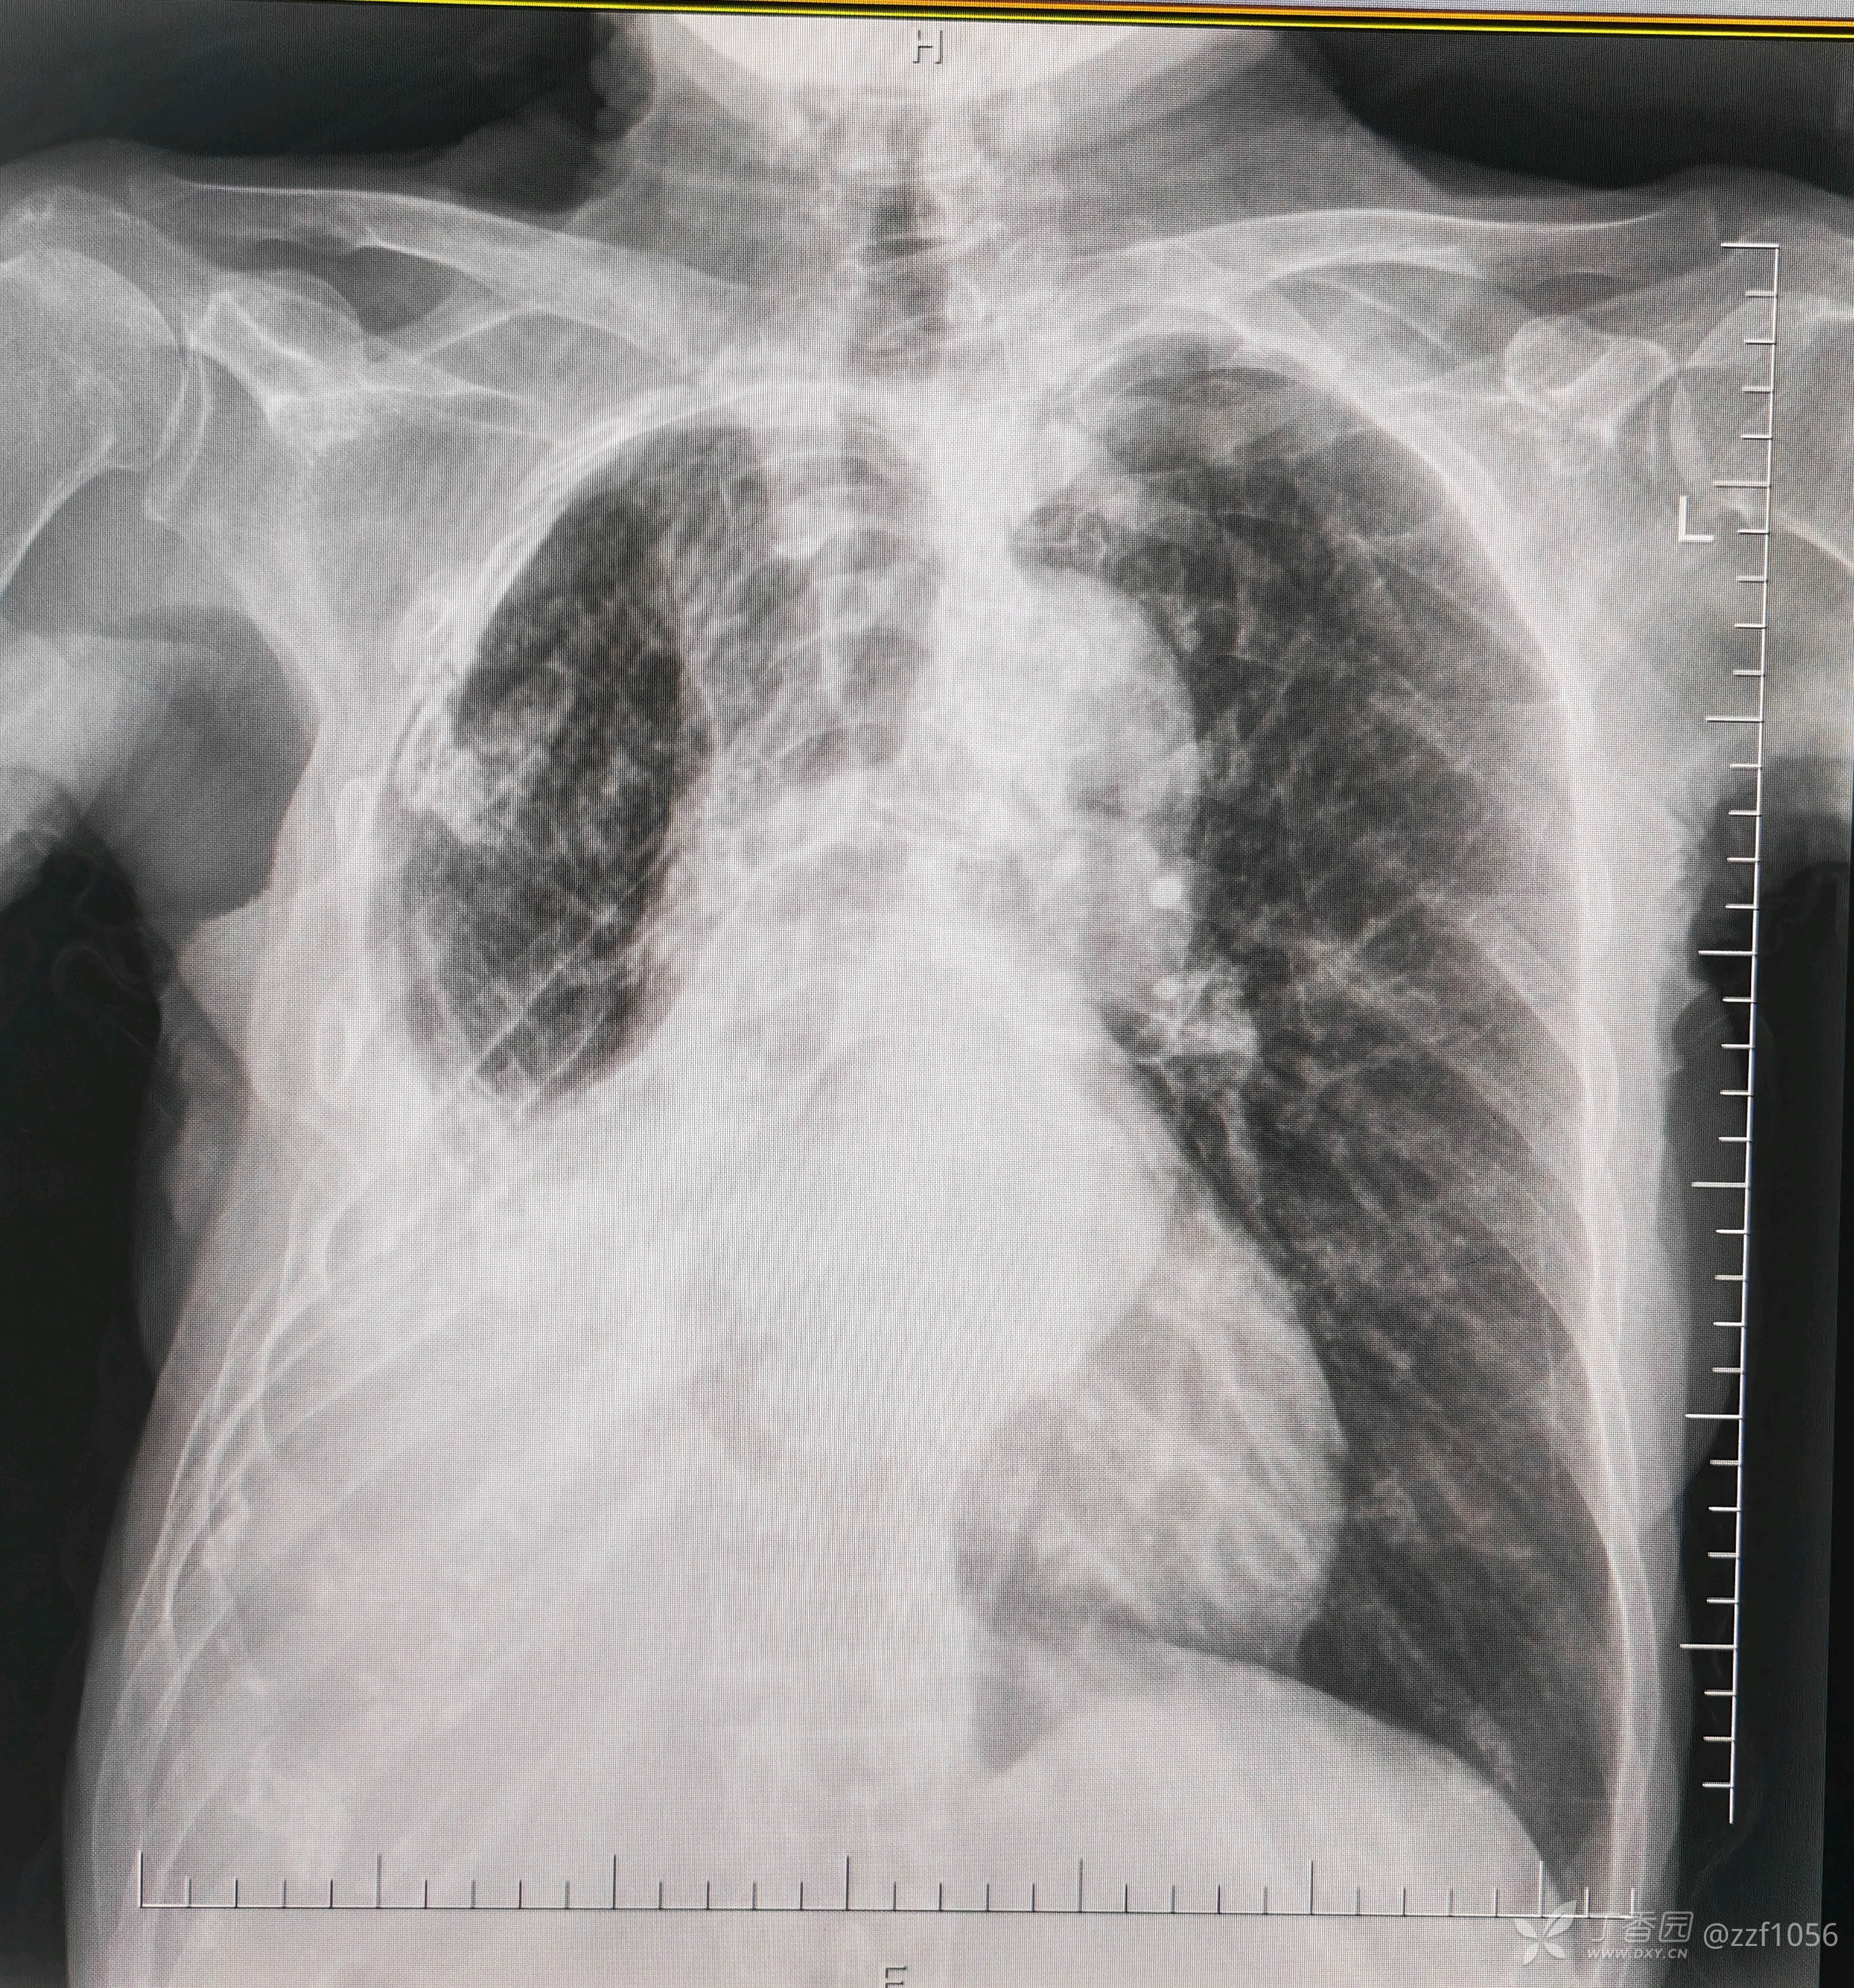

右肺不张,胸腔积液,无呼吸道症状